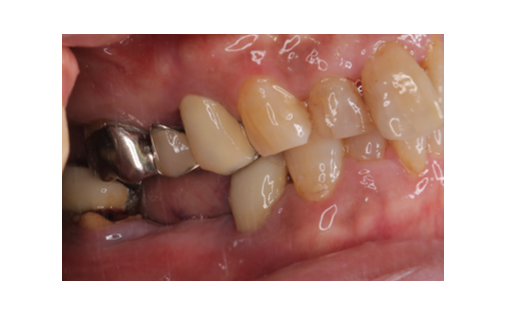

横になった親知らずの症例

Before

After